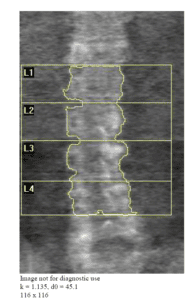

Similarly, spinal images from accredited facilities show equal amounts of soft tissue on either side of the spine with vertebrae markers precisely placed in the disk space. In non-accredited centers, the height of each vertebrae can vary considerably due to poor contrast or positioning.